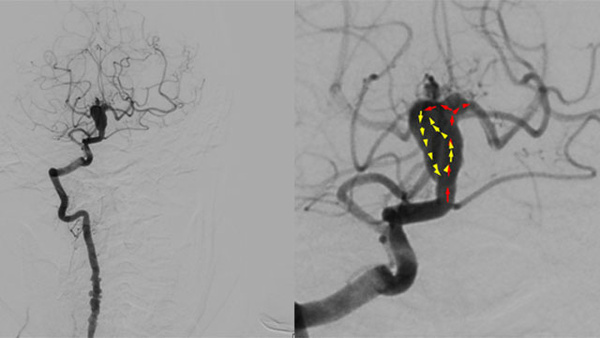

Stent assisted coilingAneurysms

September 10, 2025